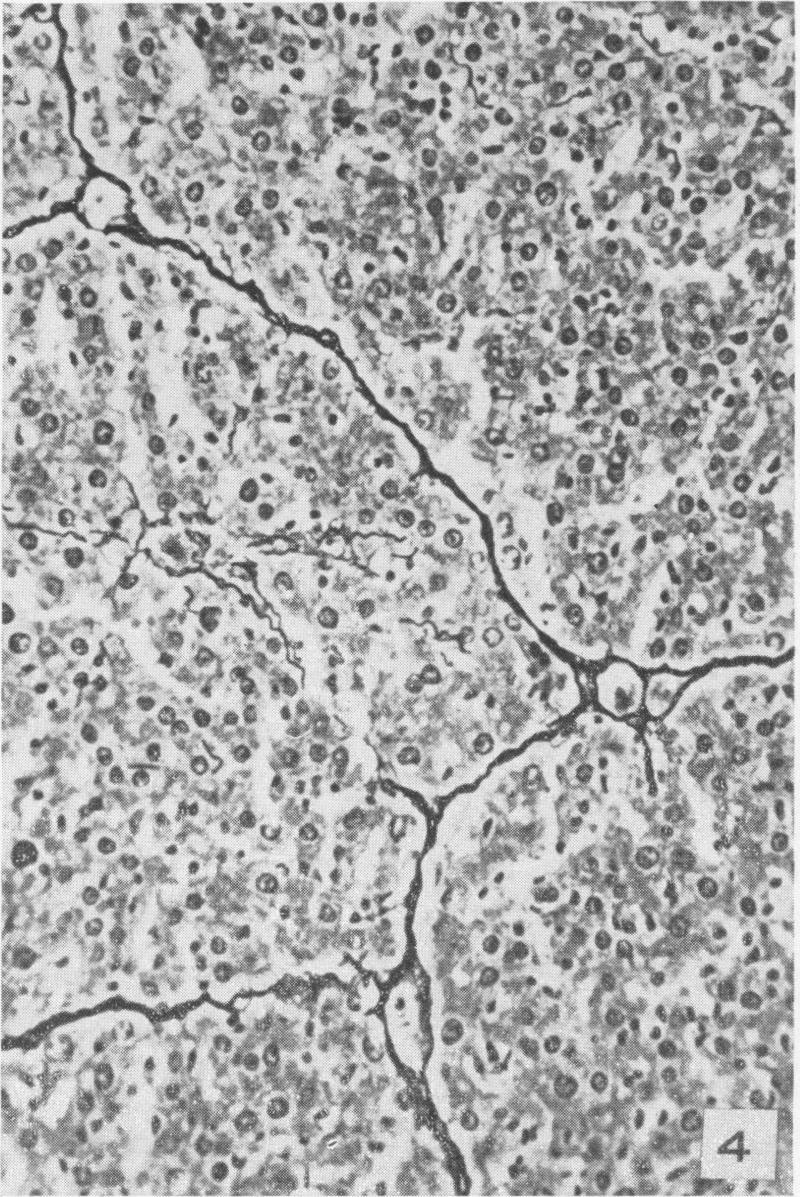

MORRIONE T G

Am J Pathol. 1949 Mar;25(2):273-85.